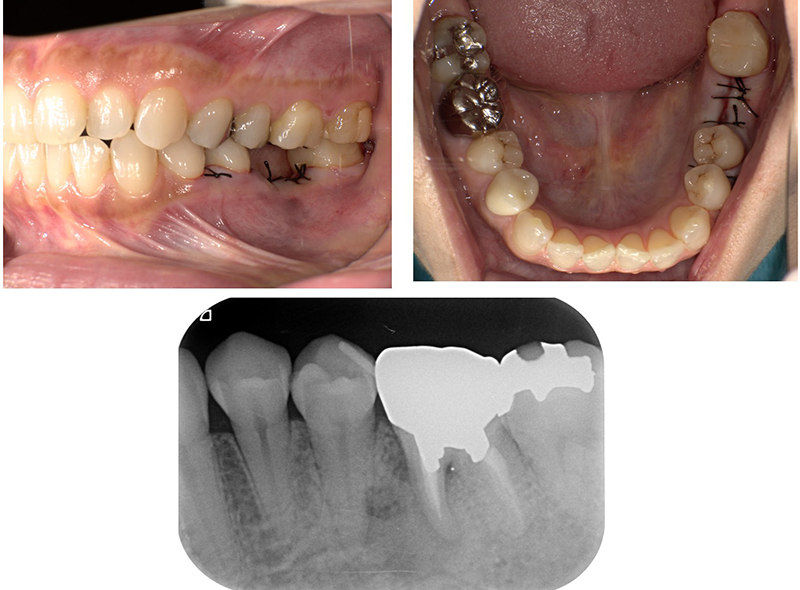

症例紹介

-

before

after

| 年齢・性別 | 47歳・女性 |

|---|---|

| 主訴 | 時々腫れるということで来院。歯根破折を認め、抜歯適応となった。欠損部分のインプラントを希望。 |

| 治療内容 | 抜歯を行い骨ができるのを待って、3ヶ月後インプラント体を埋入。更に2ヶ月後、2次オペを行い、インプラント体と骨の結合を確認したのち被せ物の型取りを行った。 その後、最終補綴物を装着した。 |

| 治療期間 | 約半年(9回) |

| 費用 | インプラント体:330,000円(税込み) 補綴物(ジルコニア)132,000円(税込み) コラーゲン使用吸収性局所止血材:4,400円(税込み) |

| リスク・副作用 | インプラント手術後は反応性の出血・腫れ・あざがでる場合がありますが、時間の経過とともに治ります。保険適応外なので、自由診療となります。 |